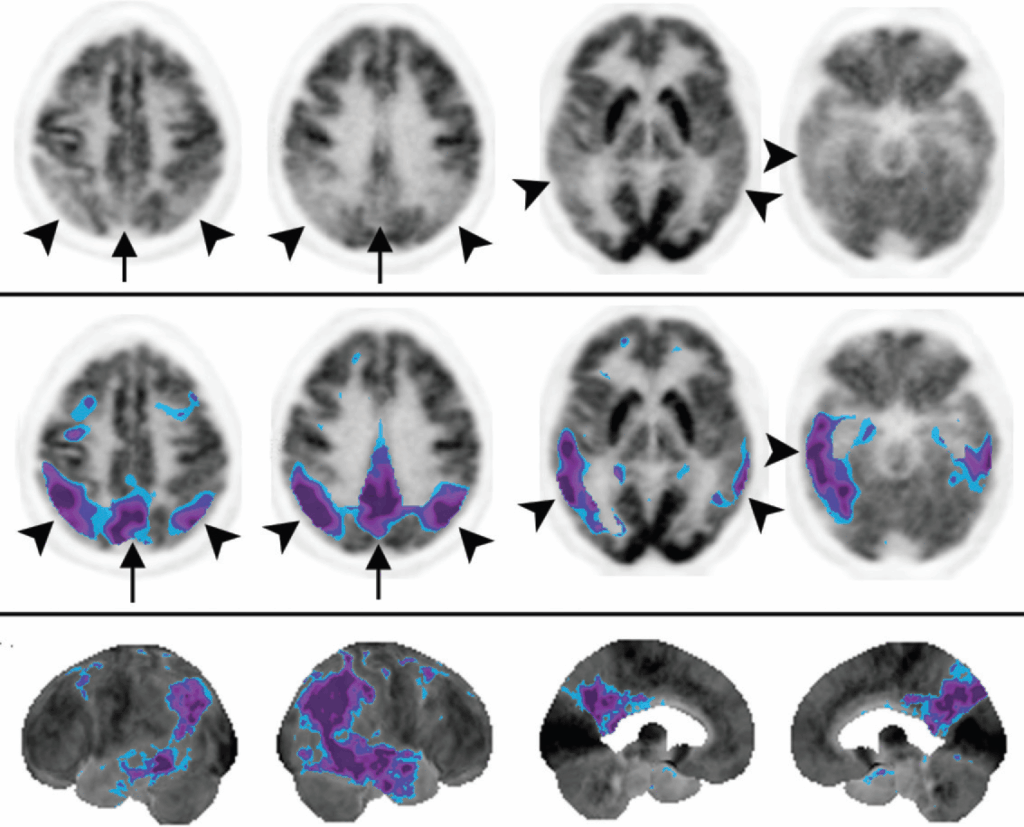

Il pattern classico della Malattia di Alzheimer è caratterizzato da un ipometabolismo che coinvolge tipicamente il giro del cingolo posteriore, il precuneo e i lobi parietali e temporali posteriori. Il coinvolgimento del giro del cingolo posteriore è un segno quasi costante e spesso il primo a manifestarsi. Le alterazioni possono essere asimmetriche. Le aree tipicamente risparmiate nella malattia di Alzheimer includono la corteccia sensomotoria, la corteccia visiva, il giro del cingolo anteriore, i gangli della base, il talamo e le strutture della fossa posteriore. Nelle fasi avanzate, l’ipometabolismo può estendersi alle cortecce associative prefrontali, ma il cingolo anteriore rimane preservato.

Durante la valutazione di un esame per sospetta demenza, è cruciale identificare e analizzare attivamente due strutture anatomiche chiave: il giro del cingolo e il precuneo. Queste aree, meglio apprezzabili sulle immagini sagittali delle superfici mediali degli emisferi, sono spesso coinvolte precocemente in molte patologie neurodegenerative.

(a) il disegno (vista parasagittale) mostra la posizione del giro cingolato (sia delle cortecce cingolate anteriore che posteriore) in arancione e della corteccia del precuneo in blu. Il precuneo è delimitato anteriormente dal ramo marginale del solco cingolato e posteriormente dal solco parieto-occipitale.

(b) L’immagine renderizzata in superficie mostra ipometabolismo da FDG nelle cortecce cingolata posteriore e del precuneo. Blu = −2 deviazioni standard, viola = −3 deviazioni standard. Il giro cingolato e il precuneo sono strutture importanti da identificare e analizzare durante la revisione delle immagini PET cerebrali con FDG ottenute in pazienti con compromissione cognitiva.